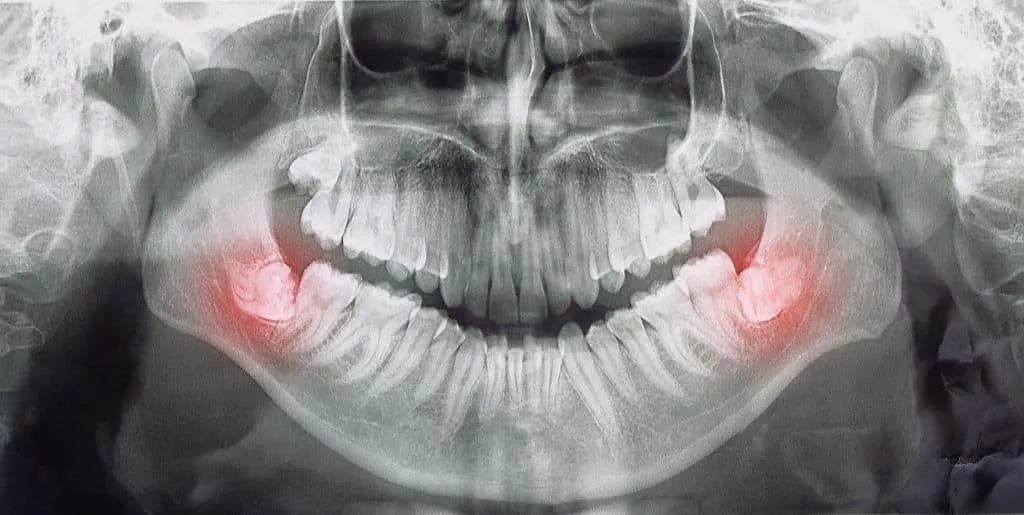

W przypadku poważniejszych problemów, takich jak zęby mądrości, może być konieczne przeprowadzenie ekstrakcji, czyli usunięcia zęba. Taki zabieg jest często zalecany, gdy ząb jest zainfekowany, uszkodzony lub powoduje ból. W Chełmie wiele klinik oferuje także nowoczesne metody znieczulenia, które sprawiają, że te zabiegi są mniej bolesne i bardziej komfortowe dla pacjentów.